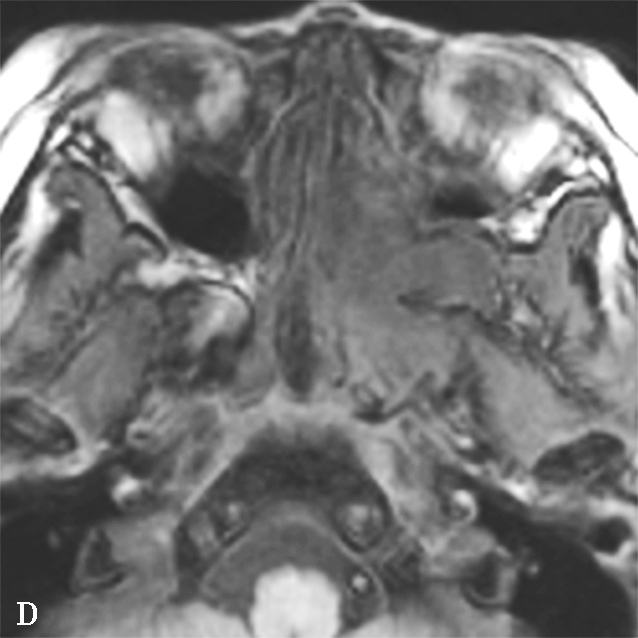

图1-2-5 青少年非角化型鼻咽癌

患者男,14岁,反复间断鼻出血、头晕头痛20余天。A.鼻窦CT横断面骨窗,示鼻咽顶后壁左侧软组织肿块,累及后鼻孔区,邻近左侧岩尖、蝶骨翼突骨质破坏、不完整,边缘毛糙;B.鼻窦CT冠状面重组骨窗,示左侧鼻咽顶后壁软组织肿块,邻近蝶骨翼突溶骨性骨质破坏,累及蝶骨体,边缘毛糙不整;C.鼻咽部MR T 2 WI横断面,示鼻咽左侧壁软组织肿块呈不均匀稍高信号,其间可见条状高信号,未见血管流空影;病变累及左侧翼内肌、窦后脂肪间隙;左侧上颌窦内可见积液呈明显高信号;D.鼻咽部MR T 1 WI横断面,示鼻咽部软组织肿块呈等信号,左侧上颌窦内积液呈低信号;E.鼻咽部MR T 1 WI横断面增强脂肪抑制序列,示鼻咽部病变呈明显强化,累及鼻咽左侧壁、顶后壁并跨越中线累及右侧咽隐窝,右侧咽后间隙淋巴结可见,与软组织肿块同步强化;F.鼻咽部MR T 1 WI冠状面增强脂肪抑制序列,示病变累及左侧咽旁间隙,左侧上颌神经明显增粗强化,并经上颌神经累及左侧海绵窦致其增厚、强化。活检病理符合鼻咽癌(非角化型)